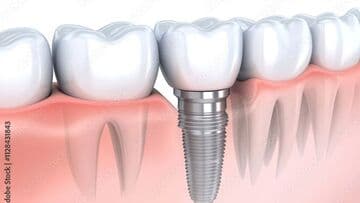

インプラントは、失った歯の部位に人工歯根を埋入し上部に人工歯を装着することで、天然歯のようにものを噛んだり、見た目を美しくすることができます。今後インプラント治療をお考えの方は、まずは、インプラントの特性を知るために、インプラントの構造や具体的なメリット・デメリットを把握する必要があると考えます。そして、ご自身の今後の治療の選択や、インプラントを埋入した後の日々のメンテナンスにその知識を役立ててもらえればと思います。

インプラントの構造について

インプラントの構造の図

インプラントと天然歯は、見た目は似ていますが、構造的には大きな違いがあります。インプラントは人工的に歯の機能を再現したものであり、天然歯とは異なる構造を持っています。

天然歯は歯髄や歯根膜に神経が通っており、温度や圧力を感じ取ることができます。しかし、インプラントには神経や歯根膜がないため感覚が鈍く、強く噛みすぎても気づきにくい、物を噛んだ時に硬い感じがするなどという感覚の違いがあります。強すぎる力がかかると、骨の吸収(骨が減る)などにつながるリスクがあるため、定期的に適切な管理が必要です。